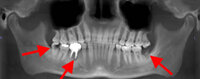

Panoramic radiograph showing decayed bilateral mandibular third molars and failed root canal treatment with periapical lesion related to the right mandibular first molar (middle arrow); also shows carious bilateral mandibular third molars on both sides

From the personal collection of Melanie S. Lang and Thomas B. Dodson